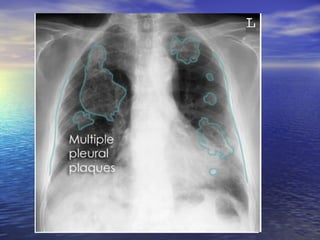

Pleural thickening Diffuse pleural thickening due to acute pleuritis :      Pneumonia      Tuberculosis      Empyema      Connective tissue disease      Drugs (eg. practolol, methysergide)      Fibrosing pleuritis      Post radiotherapy      Post-traumatic diffuse pleural thickening eg. haemothorax      Post-surgery (particularly coronary artery bypass grafting Other diagnoses that may resemble diffuse pleural thickening : Pleural plaques, Mesothelioma ,Other pleural- based tumours  Essentially all common causes of  nodular pleural thickening  are malignant and include:  mesothelioma ,  Lymphoma  ,  invasive thymoma  ,metastatic pleural disease particularly from adenocarcinomas

Pleural thickening is best seen at the lung edges where the pleura runs tangentially to the x-ray beam.  Visible pleural edge & Lung markings not visible beyond this edge Localized  pleural  thickening often occurs at the lung apices with increasing age, forming an  apical cap . This may be uni- or bilateral and is usually of homogeneous, soft tissue density, usually less than 5 mm thick, with a well-defined inferior margin. It should be distinguished from a  superior sulcus neoplasm The most useful signs in predicting the presence of malignancy are   1. Circumferential thickening 2. Nodularity 3. Thickening of greater than 1cm  4. Involvement of the mediastinal  pleura.